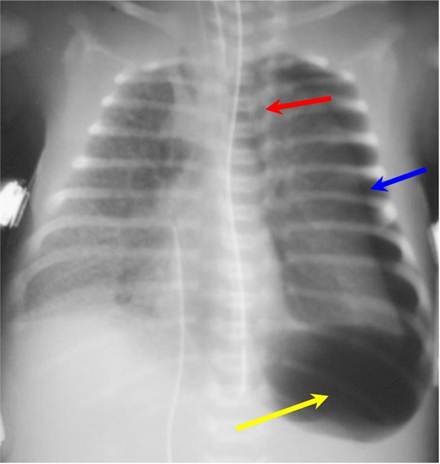

Tension pneumothorax on left (blue arrow) is displacing the heart and mediastinal structures to the right (red arrow);

this case also shows a deep sulcus sign on the left (yellow arrow). There is underlying hyaline membrane disease.

- Simple pneumothorax –no shift of the heart or mediastinal structures

- Deep sulcus sign

- On frontal view, larger lateral costodiaphragmatic recess than on opposite side

- Diaphragm may be inverted on side with deep sulcus